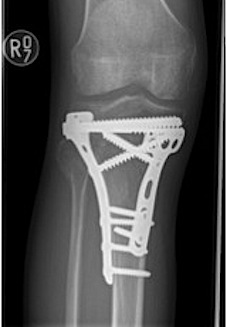

Type V Bicondylar

Options

1. Medial and Lateral plating

2. Circular Fixator

Technique

- depends on which of the three columns affected

- anterolateral approach for lateral column

- posteromedial appraoch for medial / posterior column